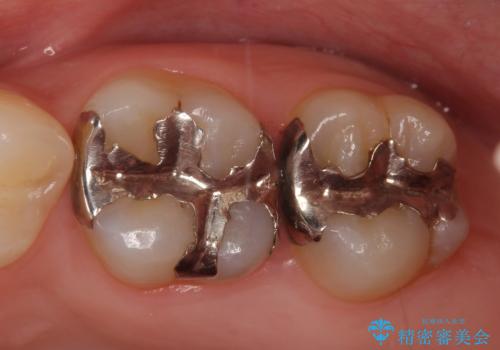

セラミックインレー 下の一番奥歯 歯ぐきの厚みを減らしてぴったりに入れます(ディスタルウェッジ+骨外科)